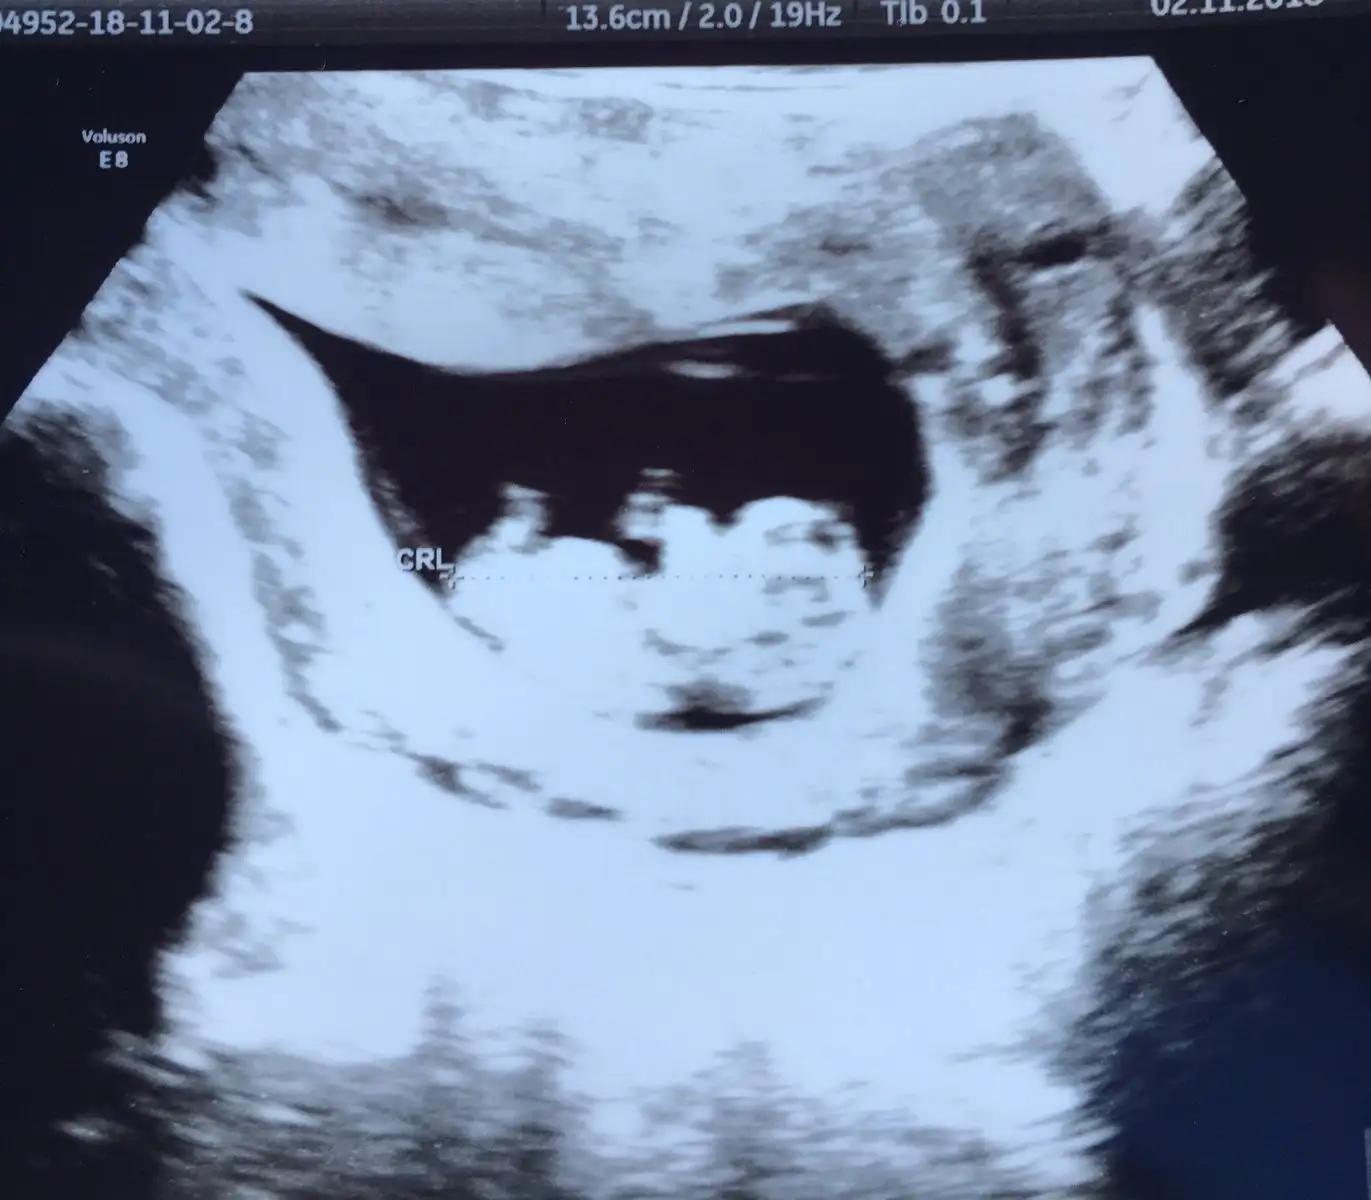

Buda benm 10+1deki ultrason fotoğrafım :) boyutları aynı sayılır sizin bebişim boyu az daha uzun gibi sankiKızlar bugün kontrole gittim.

Buda benm 10+1deki ultrason fotoğrafım :) boyutları aynı sayılır sizin bebişim boyu az daha uzun gibi sankiBu arada boyutu 3.26 cmdi